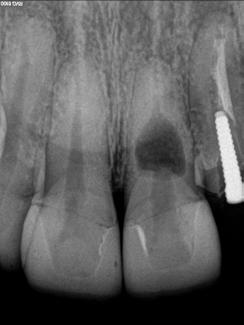

Paciente del género femenino, 44 años de edad, asistió al consultorio para realizar el retratamiento endodóntico del diente 22. Hemos hecho la radiografía inicial para evaluar el diente 22 y nos encontramos con una imagen radiolúcida en forma de globo, caracterizando una reabsorción radicular interna en el diente 21. Hemos hecho, entonces, una nueva radiografía para evaluar el diente 21 (Figura 1).

Figura 1 - Radiografia inicial

Durante la anamnesis la paciente relató haber sufrido un cabezazo del hijo hace dos años. El examen clínico reveló presencia de faceta de porcelana en el diente 21, prueba de sensibilidad pulpar positiva, ausencia de sintomatología y ausencia de alteraciones en la mucosa gingival. Solicitamos una tomografía computarizada cone beam (Figuras 2, 3 y 4) para confirmar el diagnóstico, evaluar si la reabsorción era comunicante o no y para estudiar la estructura dental radicular remanente.